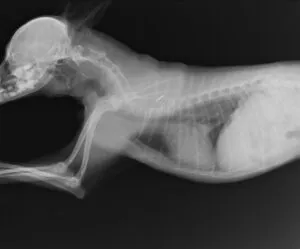

レントゲン検査を行うと腫瘤底部の上顎骨の溶解像が認められた。肺への転移は認めなかった。